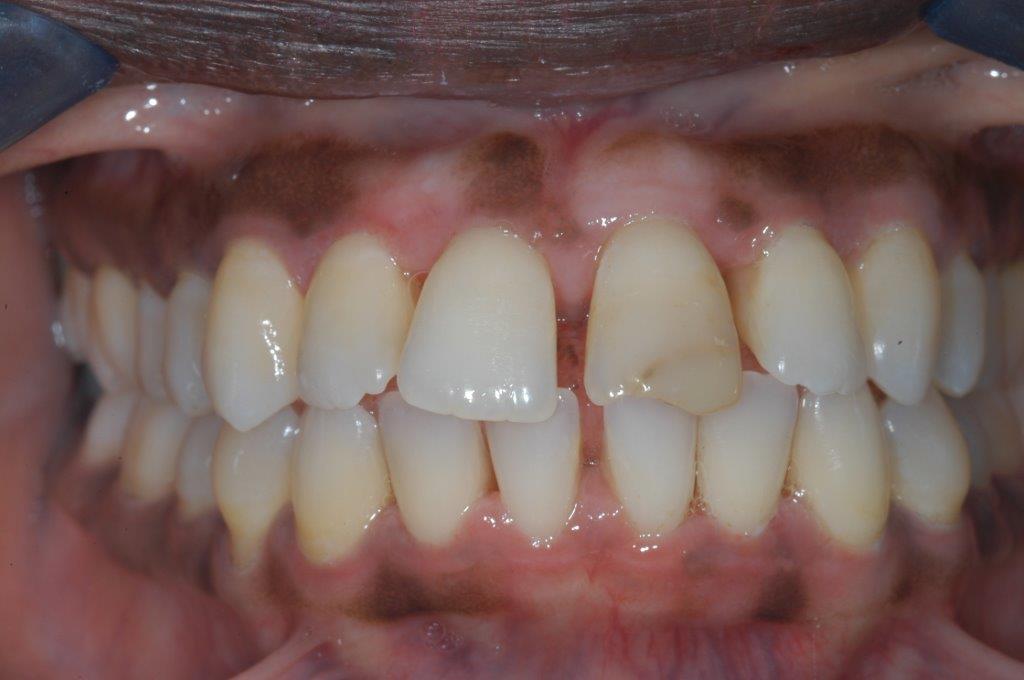

This patient experienced many areas of gum recession, primarily on the upper and lower front teeth. This patient's own tissue was used to correct the problem.